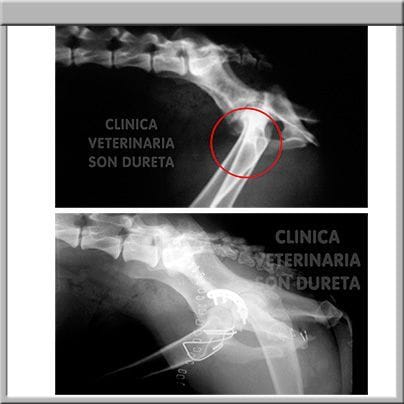

Pancho requería una actuación veterinaria intensiva y urgente, inmediatamente se administraron fluidos por vía intravenosa y una transfusión de plasma, con el objetivo de corregir su deshidratación, coagulación y restaurar su volumen de líquido circulante. Le aplicamos calor para recuperar su temperatura corporal y toda la medicación de apoyo necesaria para ayudar a su estómago e intestinos a recuperarse (protectores gástricos, antibióticos, analgésicos, protectores hepáticos y vitaminas).